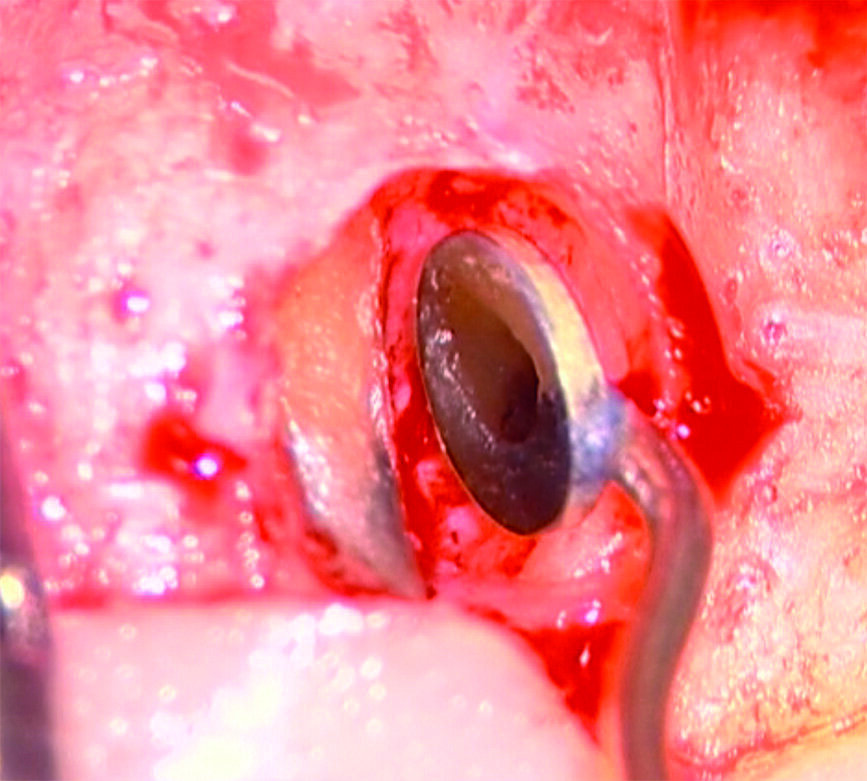

Perforazioni del terzo coronale e delle biforcazioni

Tali perforazioni sono piuttosto frequenti a livello degli incisivi superiori, dove l’errore che più spesso viene commesso è rappresentato dall’utilizzo della fresa con eccessiva angolazione vestibolare. Perforazioni del terzo coronale possono anche accadere sul pavimento dei molari quando gli orifizi canalari vengono cercati in posti sbagliati. Tipiche sono le perforazioni nei molari superiori o inferiori, che avvengono per lo sfondamento del pavimento della camera pulpare (Figg. 3a-3i). Come conseguenza del trauma meccanico, si ha una rapida distruzione del legamento parodontale. L’osso alveolare immediatamente adiacente alla perforazione si riassorbe con conseguente perdita verticale di osso. Il processo infiammatorio quindi si estende coronalmente lungo le fibre del legamento parodontale, con distruzione del legamento, dell’osso alveolare e delle fibre gengivali sopracrestali. Come conseguenza di ciò, si ha la migrazione apicale dell’attacco epiteliale e le formazione di un grave difetto parodontale9.